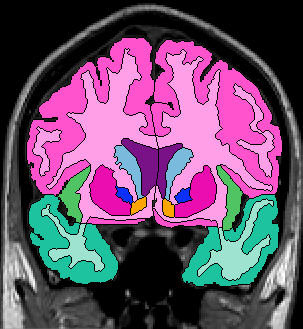

The insular cortex is “hidden” between the temporal and inferior parietal corticies. By drawing sulci lines in the sagittal view, we gain an outline of it in the coronal. Choose a sagittal slice where insula is clearly visible (Fig 1), then draw a “circle” around it (Fig 2). Do this for several slices and for both hemispheres.

Figure 1              Figure

2

Once you have drawn your sulci lines, the insula should be clearly outlined (by little dots) in the coronal view (Fig 3). This is particularly useful in the more anterior slices.

Figure 3